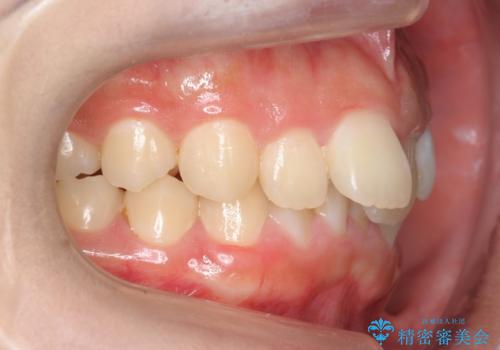

治療結果には大変満足されていました。

笑っても大きく歯ぐきが見える方ではなかったので、歯ぐきのラインが目立つことはなかったです。

手術をしなければ左上1番の歯頚ラインは左上2番よりも短い位置になっていたため、歯自体の長さが不自然なほど短くなってしまったと思います。

矯正治療もご自身の歯を生かしていけますが、後戻りの問題や、前歯のみを動かすことが不可能なため、セラミック治療と同じくメリット、デメリットがあります。